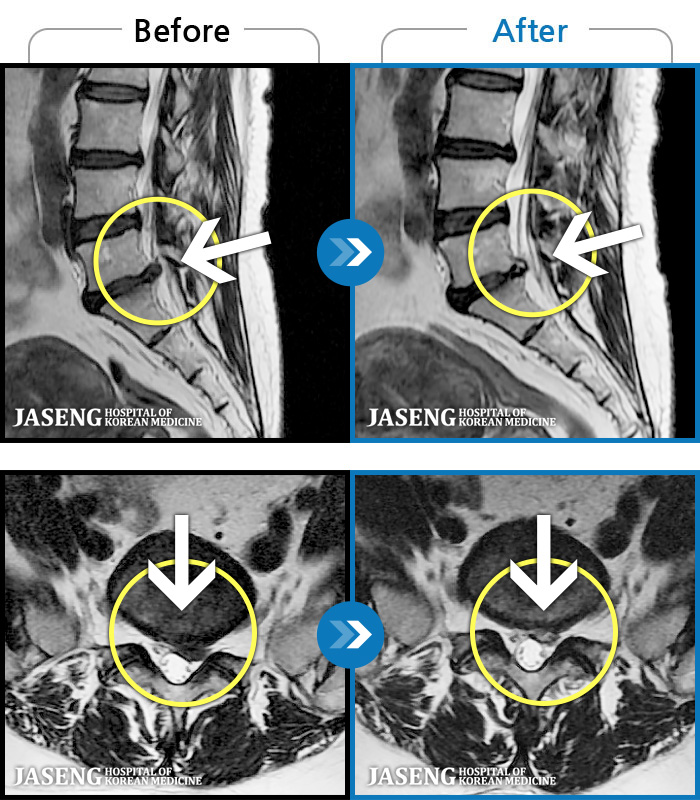

Xray 와 MRI 검사를 받았고

4번5번 척추사이 협착증과 유종이 원인이라고 하면서

한방 비수술치료로 2달동안 치료하면 나을 수가 있다고 말씀하셨고, 만약 한방치료로도 낫지 않으면 큰 대학병원 수술을 받아야 한다고 하면서 한방 비수술 치료를 권장해 주셔서, 박정우원장님의 치료를 받기 시작하였다.

신바로약침, 봉침, 청파전한약으로 한 달 정도 치료를 받으니 통증이 덜하고 점차 걸을 수 있는 거리가 늘어가기 시작하였다.

12월20일까지 두 달 정도 치료를 마친 결과,

거의 정상상태로 회복 되었으며, 현재는 집에서 꾸준하게 체조와 가벼운 운동으로 관리하고 있습니다.